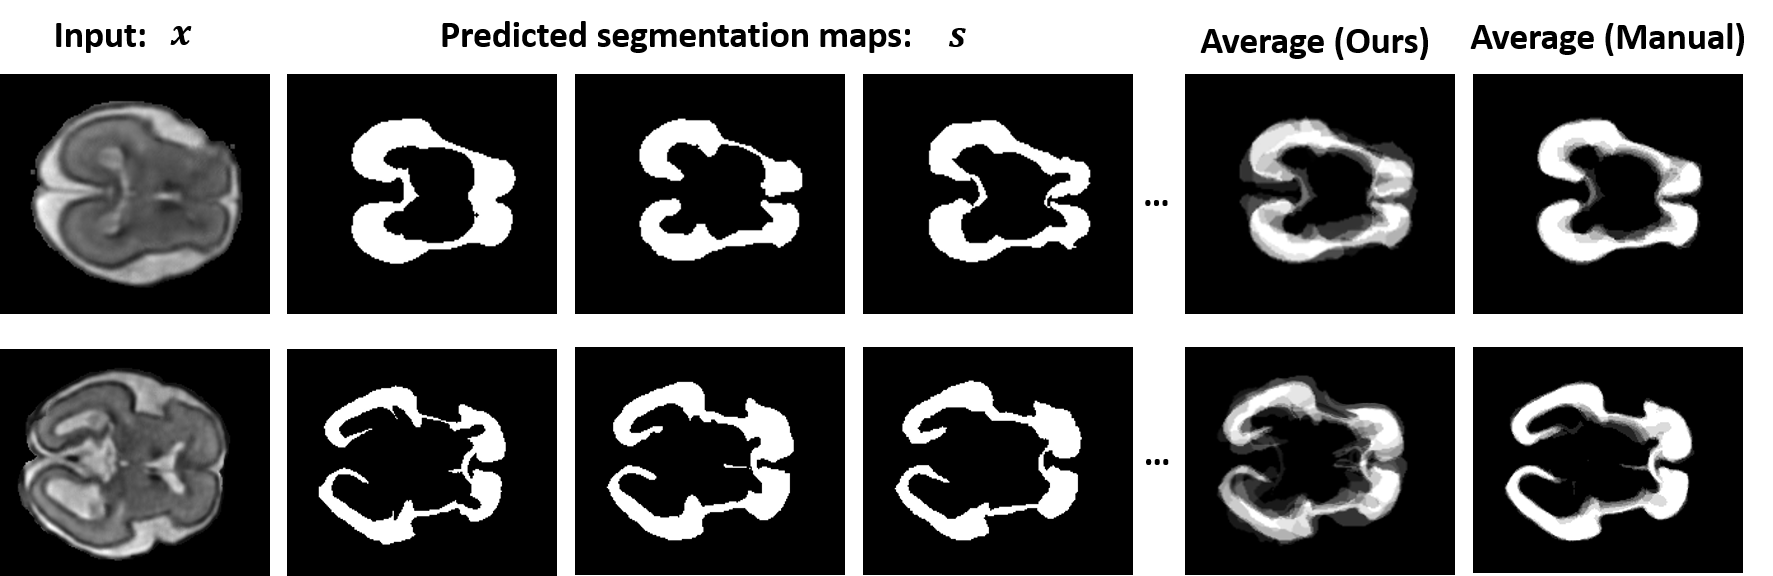

Lesions or organ boundaries visible through medical imaging data are often ambiguous, thus resulting in significant variations in multi-reader delineations, i.e., the source of aleatoric uncertainty. In particular, quantifying the inter-observer variability of manual annotations with Magnetic Resonance (MR) Imaging data plays a crucial role in establishing a reference standard for various diagnosis and treatment tasks. Most segmentation methods, however, simply model a mapping from an image to its single segmentation map and do not take the disagreement of annotators into consideration. In order to account for inter-observer variability, without sacrificing accuracy, we propose a novel variational inference framework to model the distribution of plausible segmentation maps, given a specific MR image, which explicitly represents the multi-reader variability. Specifically, we resort to a latent vector to encode the multi-reader variability and counteract the inherent information loss in the imaging data. Then, we apply a variational autoencoder network and optimize its evidence lower bound (ELBO) to efficiently approximate the distribution of the segmentation map, given an MR image. Experimental results, carried out with the QUBIQ brain growth MRI segmentation datasets with seven annotators, demonstrate the effectiveness of our approach.